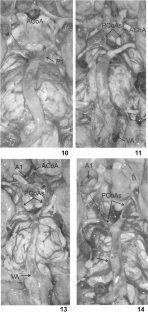

Fig. 1

Fig. 2

Fig. 3

Fig. 4

Fig. 5

Fig. 6

Fig. 7

Fig. 8